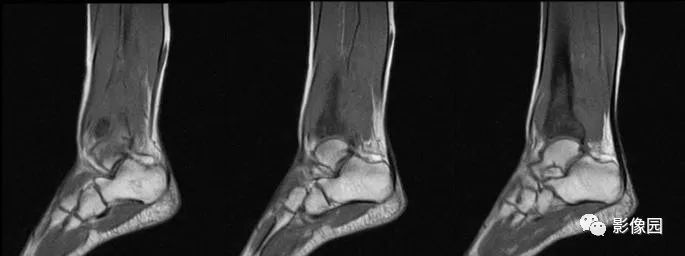

2016-05-11复查

评论:前片X线示左胫骨下段及干骺端病变,髓腔内密度不均匀增高,内侧骨皮质可见骨质破坏,可见骨膜反应。CT示病灶内见多发斑片状肿瘤骨(黄色箭头),周围可见针状骨膜反应(红色箭头)。周围软组织肿胀。MRI示胫骨下段以长T1、长2信号为主的混杂信号影,未跨越胫距关节面,周围未见明显软组织肿块。周围软组织广泛片状长T1长T2信号影。复查X线示病变较前片明显进展,左侧胫骨远段及干骺端骨质破坏,周围可见针状骨膜反应及Codman三角(蓝色箭头)形成。相邻左侧腓骨下端、距骨滑车受累。